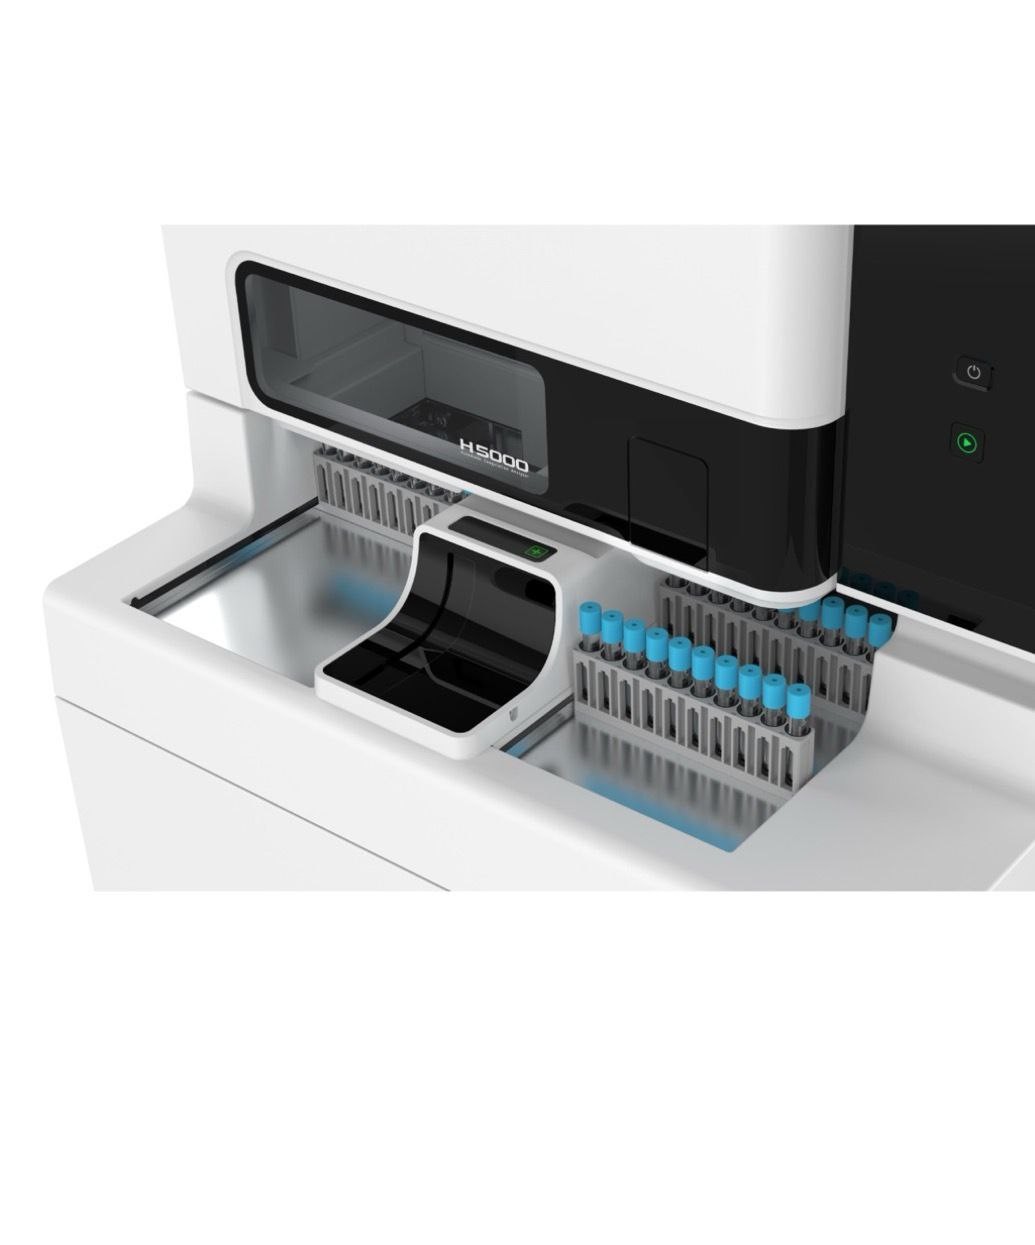

H5000全自动凝血分析仪

项目类型

器械质押区

起投金额

21000USDT

每日释放:1.3

释放周期:162 天

已购: 7142

剩余: 0